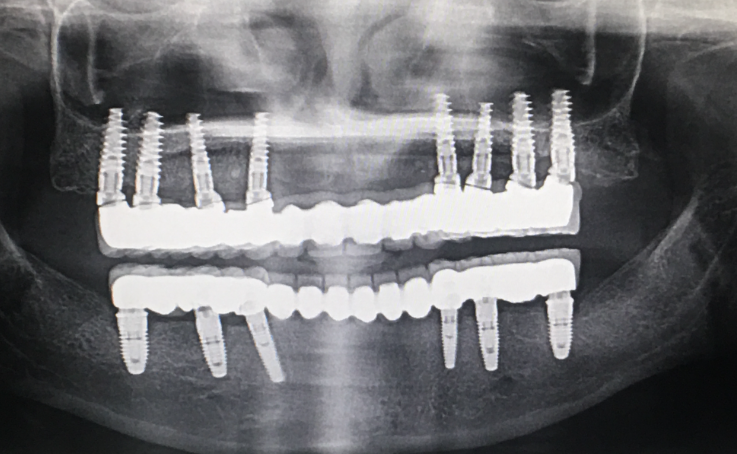

02. 풀마우스 임플란트

말 그대로 임플란트로 전체를 진행하는 것을 말합니다. 위턱과 아래턱 각각 최소 8개 이상의 임플란트를 식립하게 되는데요. 그렇기 때문에 가격적으로 비싸질 수 밖에 없습니다.

하지만 그만큼 차원이 다른 사용감과 저작력을 자랑하며, 흡사 자연치아와 같은 사용감을 느낄 수 있다고 합니다. 그리고 틀니같은 경우는 문제가 생기면 틀니 자체를 바꿔야하지만, 임플란트는 개별적인 관리가 가능하며, 수명이 길어 오래오래 사용하실 수 있을 것입니다.